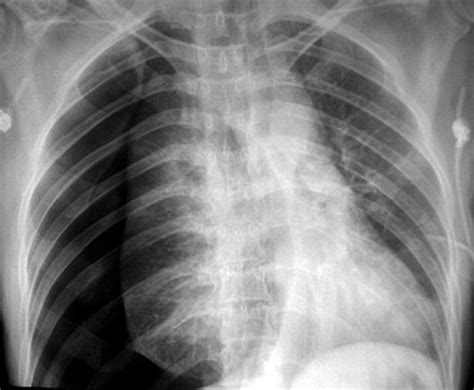

A pneumothorax, commonly referred to as a collapsed lung, is a medical condition where air leaks into the space between the lung and the chest wall. This accumulation of air exerts pressure on the outside of the lung, preventing it from fully expanding. When a patient presents to an emergency department with symptoms like sudden sharp chest pain or shortness of breath, a pneumothorax X-ray is typically the first diagnostic tool utilized by medical professionals to confirm the diagnosis and determine the severity of the collapse.

The pneumothorax X-ray is the gold standard for initial imaging because it is quick, widely available, and highly effective at visualizing the air pocket that characterizes this condition. While specialized imaging like a CT scan might be required for complex cases, a standard upright posteroanterior (PA) chest X-ray provides sufficient detail for most clinical decisions.

When reviewing the film, radiologists look for the "visceral pleural line." This is the thin, sharp white line that represents the edge of the collapsed lung. Beyond this line, there are no visible lung markings—this area appears darker because it contains air but no lung tissue.

It is important to note that the size of the pneumothorax is often estimated by measuring the distance between the lung margin and the chest wall at the level of the hilum. This measurement helps clinicians decide whether the patient needs observation, aspiration, or the insertion of a chest tube.

• Absence of lung markings: Peripheral areas of the lung field will appear hyper-lucent (darker) because the air is trapped in the pleural space rather than within the lung alveoli.

• Visceral pleural line: A thin, distinct line separating the collapsed lung from the air-filled pleural space.

• Deep sulcus sign: On a supine X-ray, air may collect anteriorly and inferiorly, making the costophrenic angle appear abnormally deep and dark.

• Mediastinal shift: In cases of tension pneumothorax, the pressure may become so high that it pushes the heart and trachea toward the opposite side of the chest.